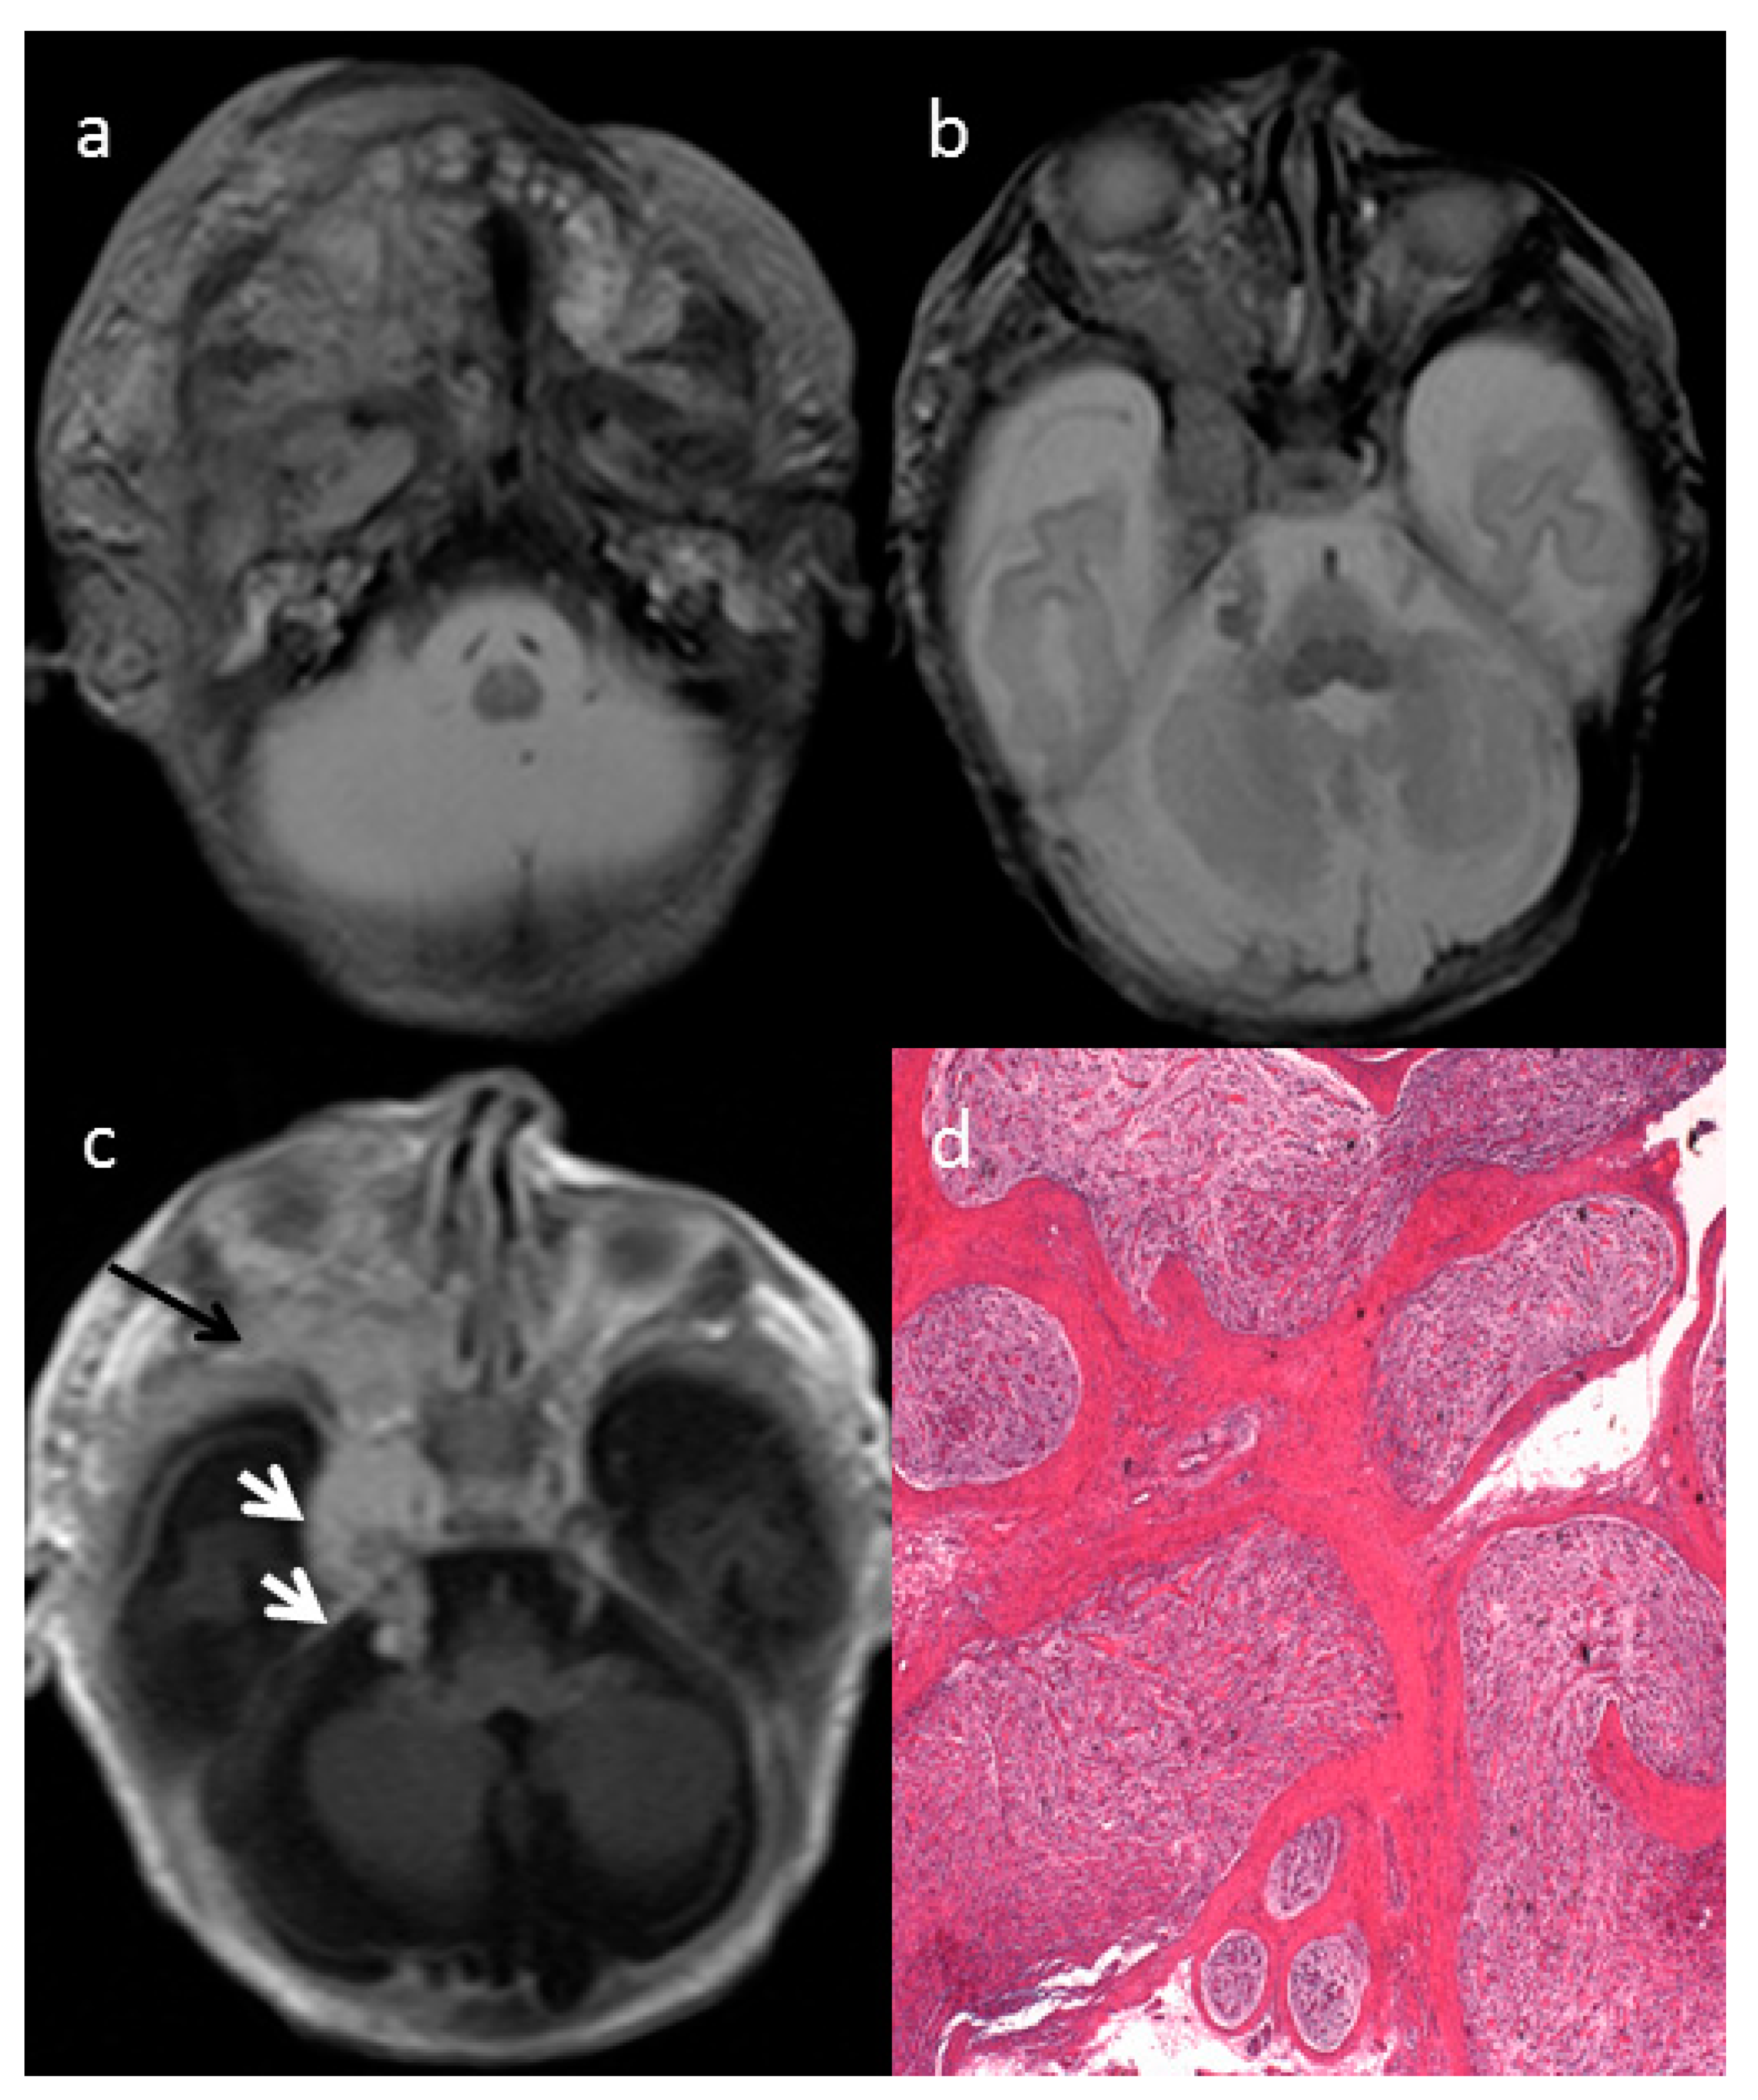

Diagnostics Free FullText Congenital Craniofacial Plexiform Cutaneous Neurofibromatosis Electrodessication People with neurofibromatosis type 1 (nf1) suffer disfigurement and pain when hundreds to thousands of cutaneous. Cutaneous neurofibromas (cnfs) are physically disfiguring, are painful, and cause extensive psychologic harm in patients with. The use of electrodessication in the treatment of cutaneous neurofibromatosis: Intraoperative photograph showing the use of monopolar diathermy for electrodessication of cutaneous neurofibromas. Cutaneous Neurofibromatosis Electrodessication.